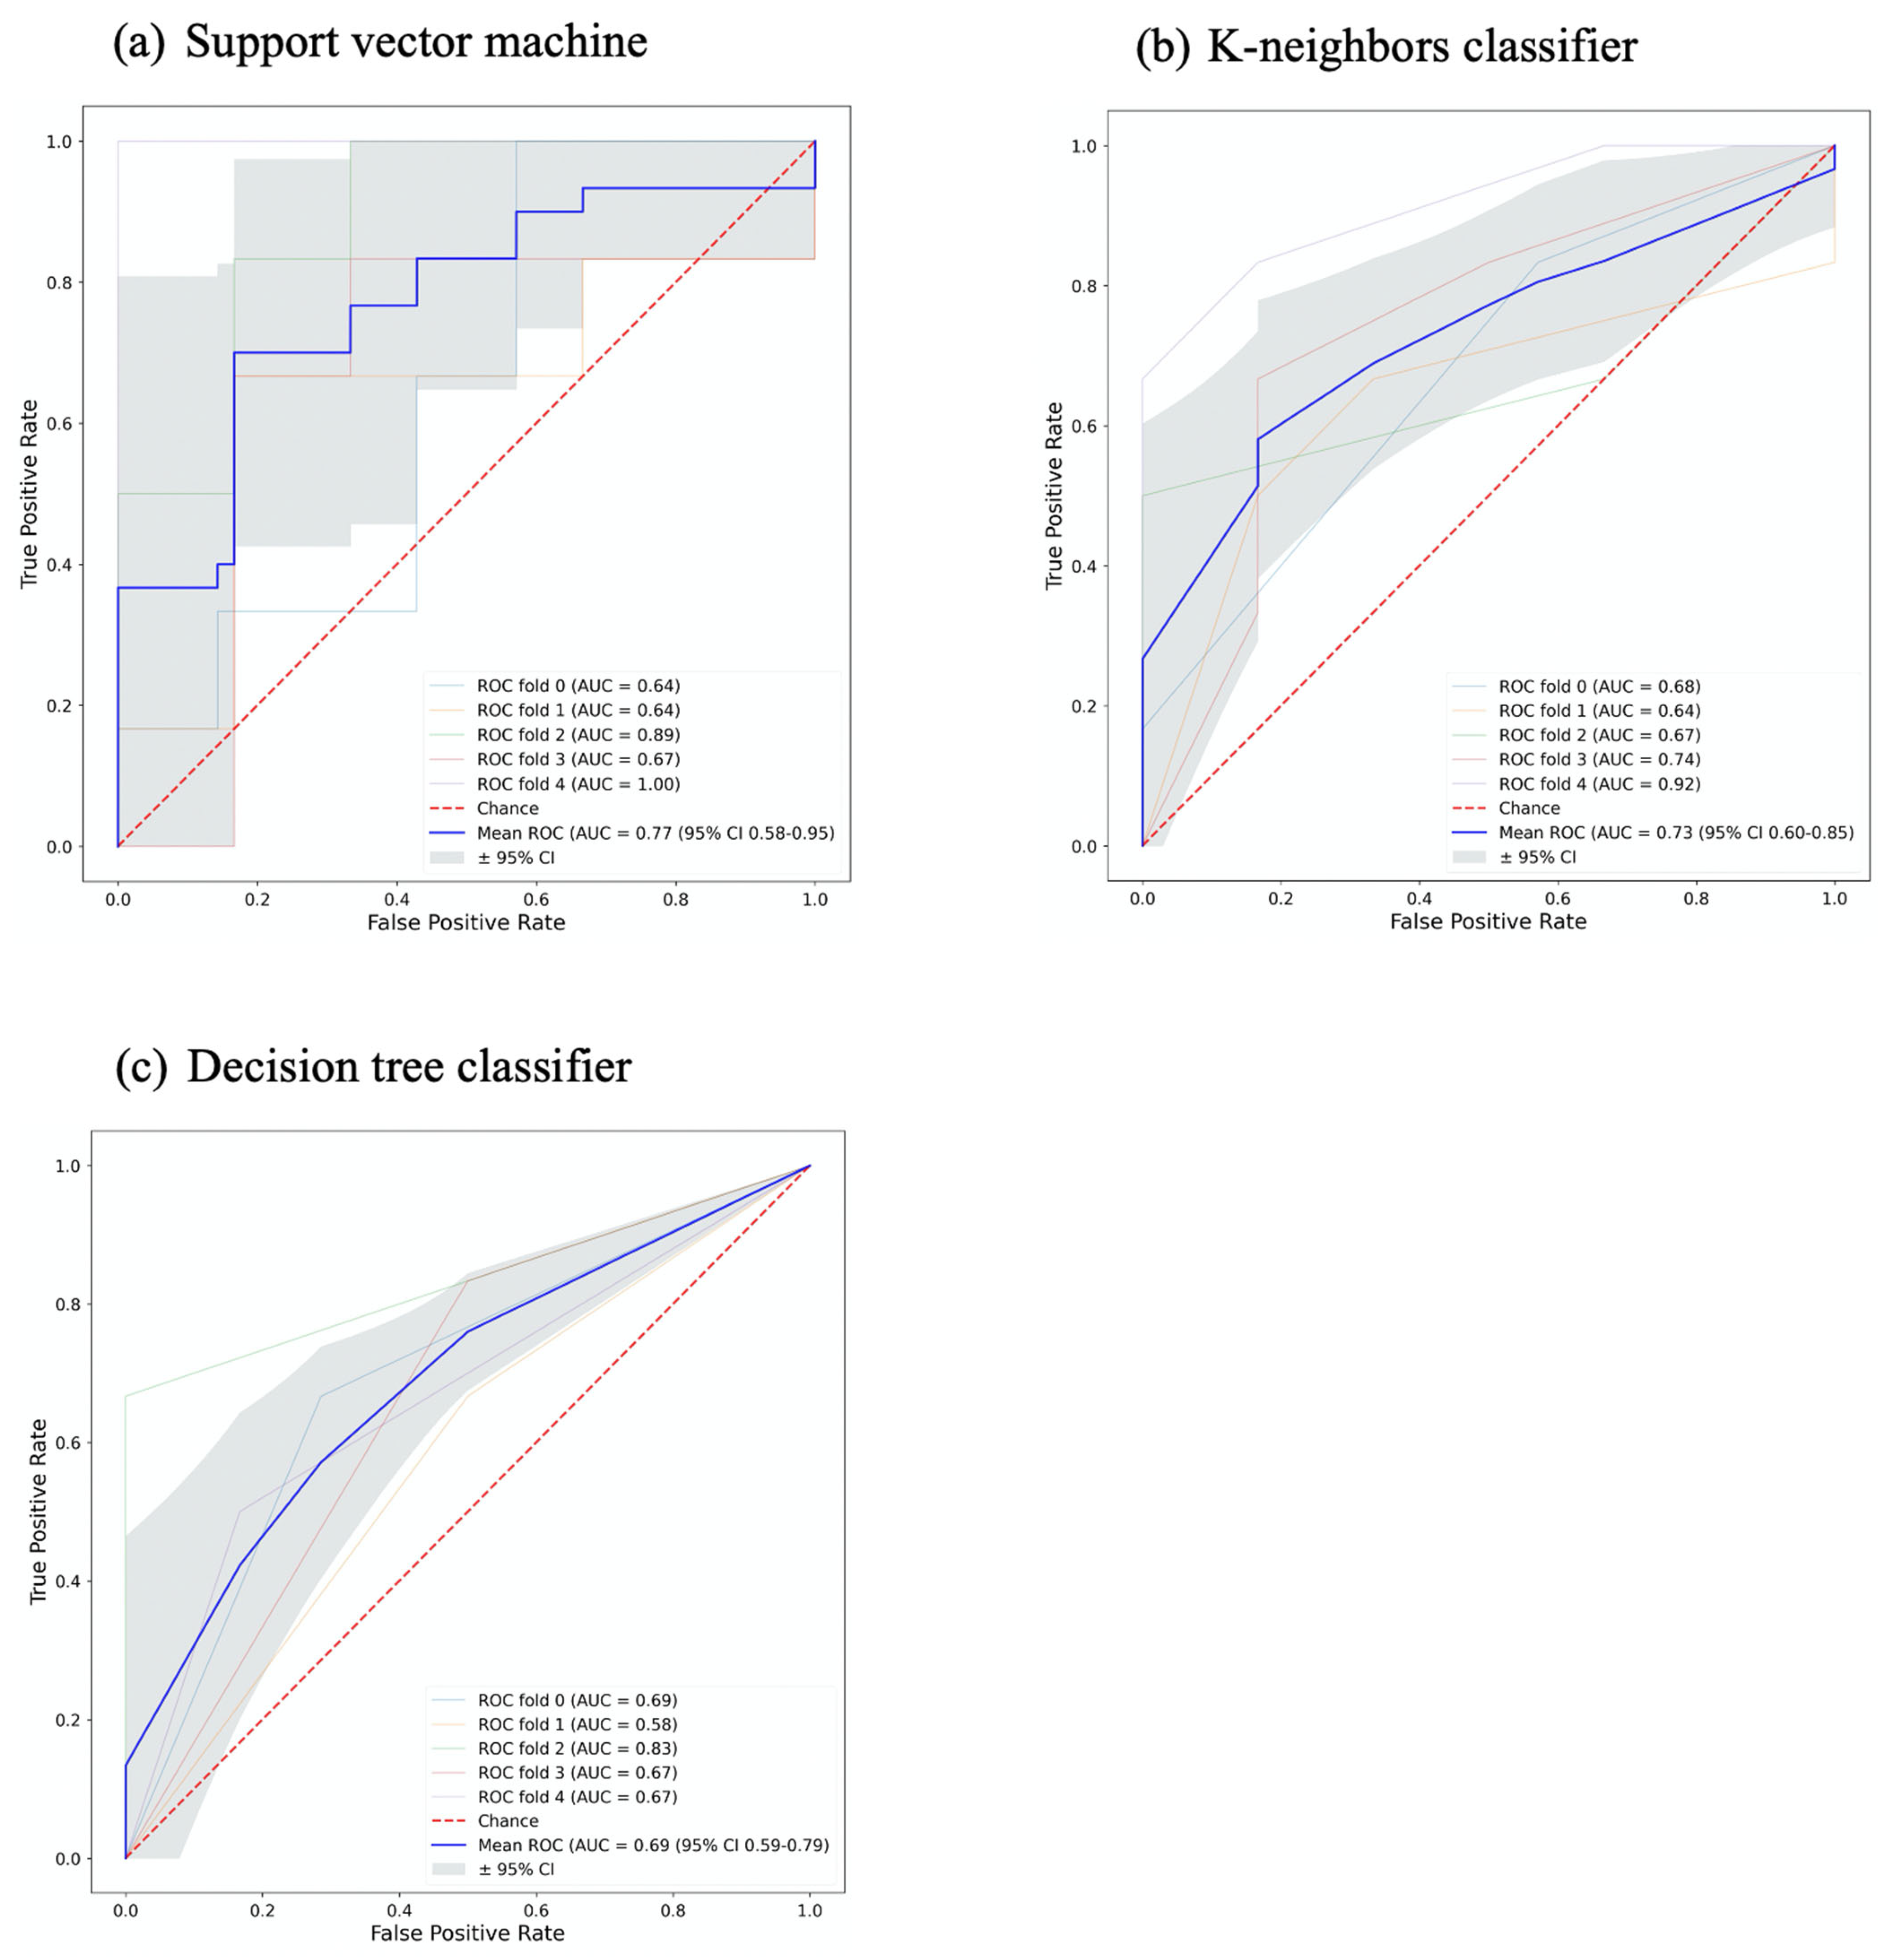

3.2. Signature Building and Machine Learning Performance